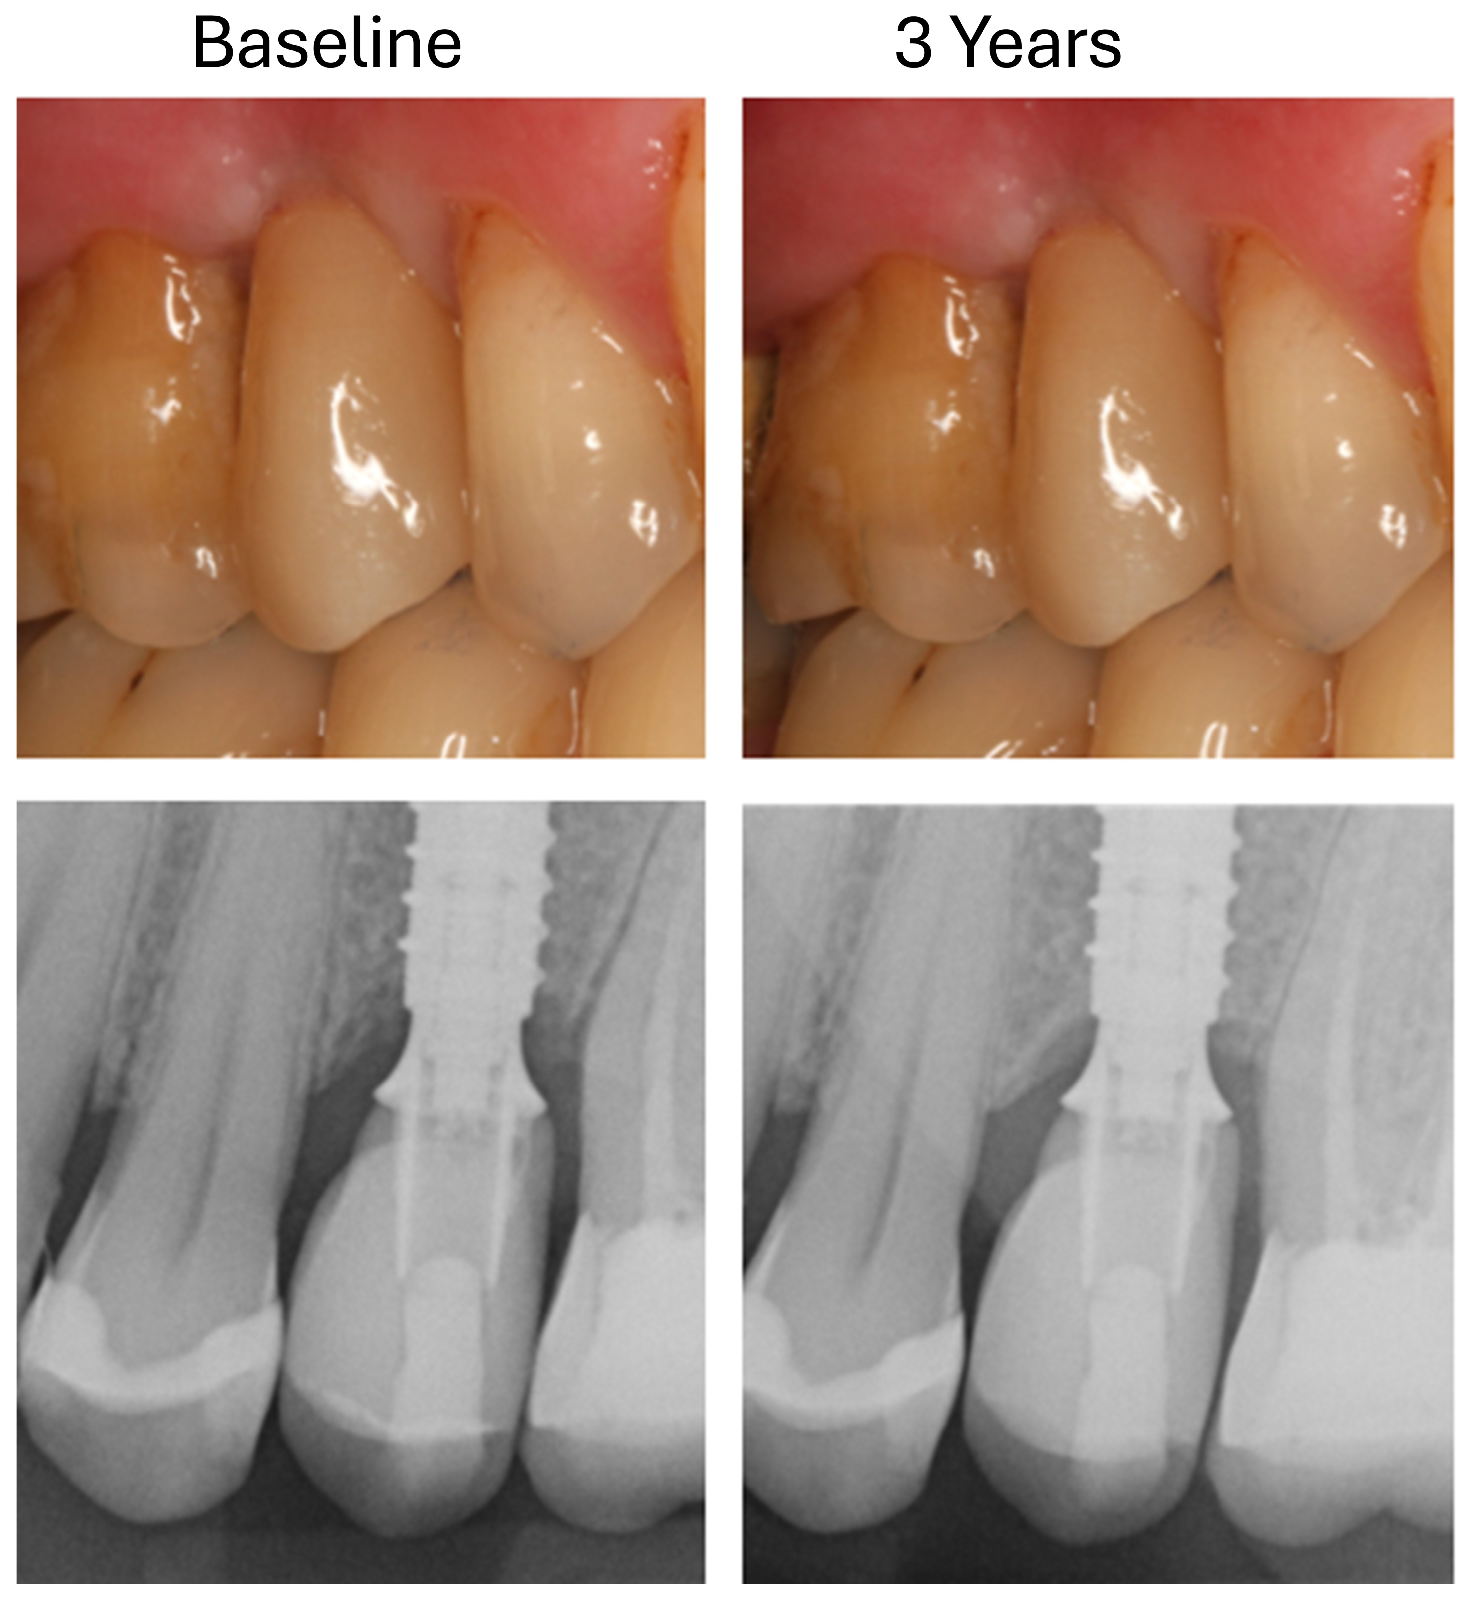

- T0: 1 week after insertion of the superstructure (baseline);

- T1: 3 years after implantation.

3.3. Changes in Marginal Bone Profile

3.4. Technical Complications